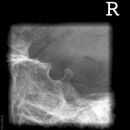

Kieferköpfchen nach Schüller

Lagerung

Bauchlage, d.h. stabile Seitenlage, wie Schädel seitlich

zu untersuchende Seite aufliegend

Zentralstrahl

Zielt mit ca. 20° cranio-caudal auf das aufliegende Ohr (Zur Hilfe kann das detektorferne Ohr verwendet werden, welches auf die Platte projiziert wird.)

Qualitätskriterien

Freier Einblick auf das Kiefergelenk.